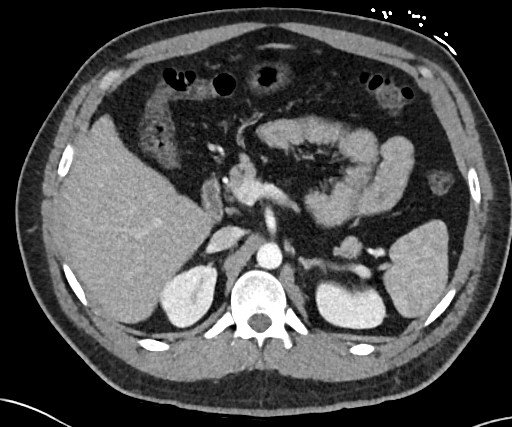

The Axial View

The word axis is a Latin in origin, meaning ‘axle’ or ‘pivot’. An axial plane is perpendicular to the long axis of the human body (an imaginary vertical line running from head to toe). In fact, in the early days, CT was known as CAT scan (Computed Axial Tomography).

Picture the image slice moving from the toes to the head; the left side of the screen corresponds to the patient’s right side.

We often start with the axial view, then try to validate what we are seeing with the other 2 views.